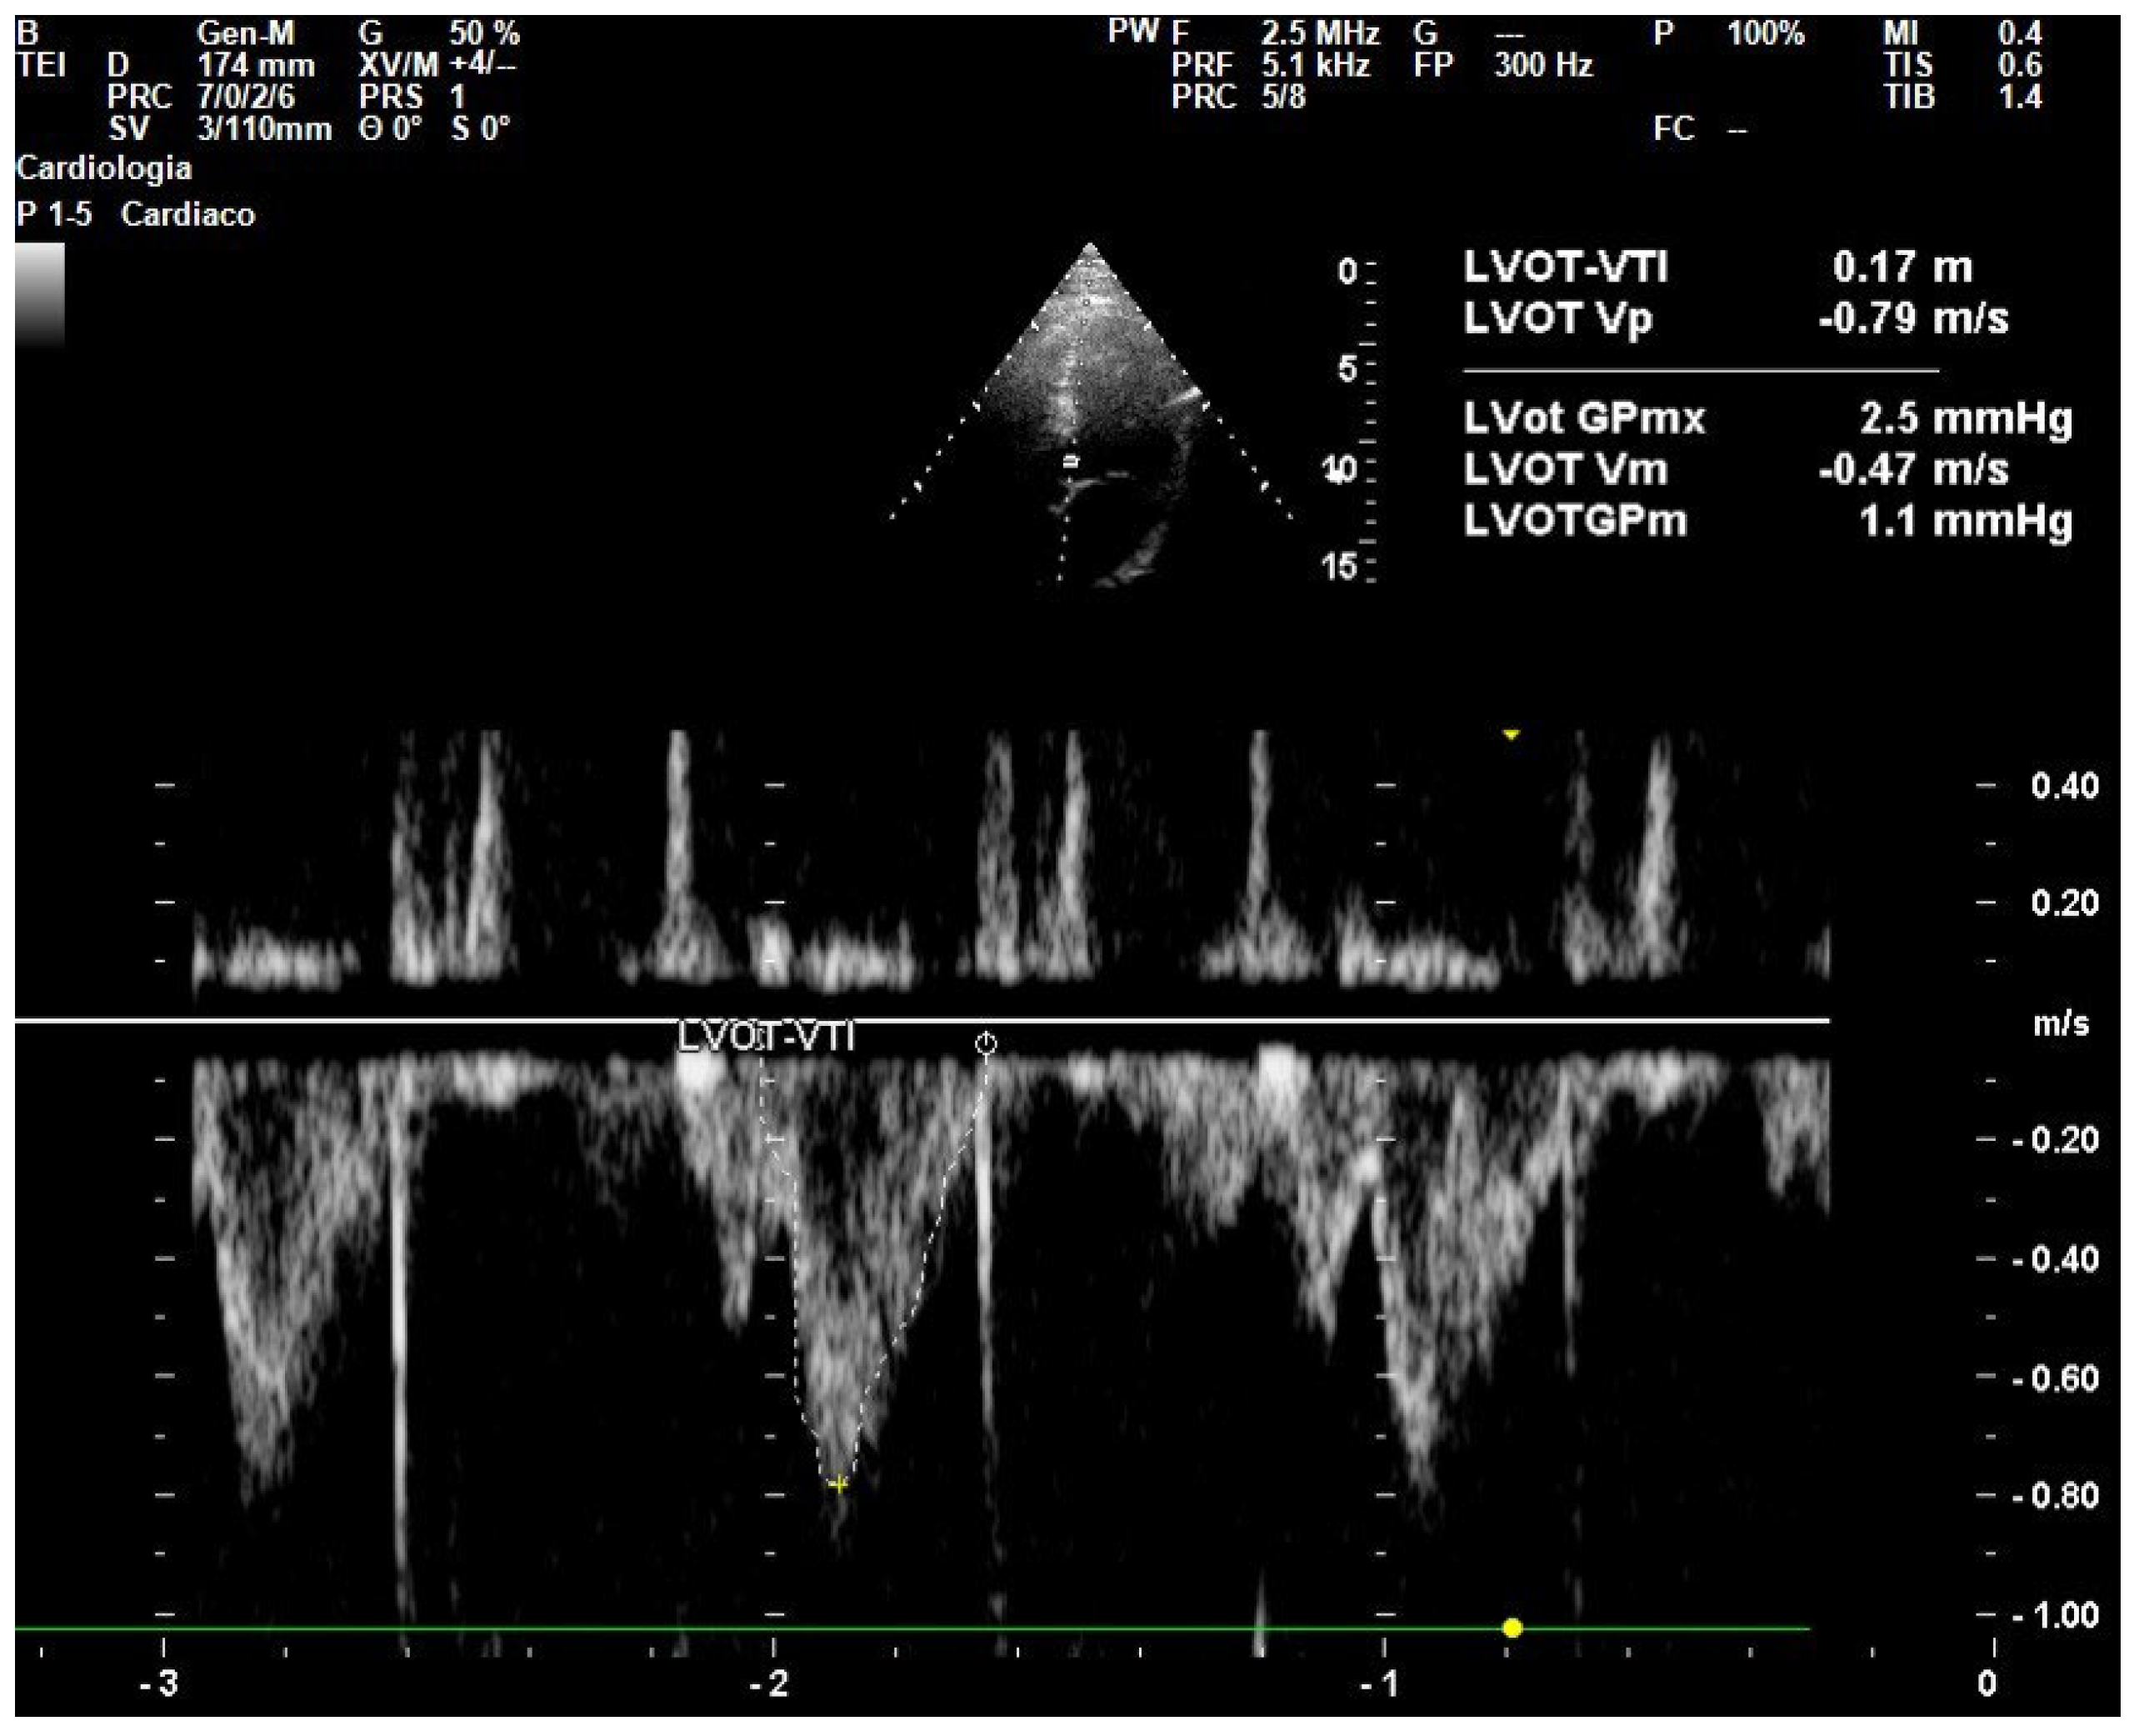

- Wang, J.; Zhou, D.; Gao, Y.; Wu, Z.; Wang, X.; Lv, C. Effect of VTILVOT Variation Rate on the Assessment of Fluid Responsiveness in Septic Shock Patients. Medicine 2020, 99, e22702. [Google Scholar] [CrossRef]

- Parker, C.W.; Kolimas, A.M.; Kotini-Shah, P. Velocity-Time Integral: A Bedside Echocardiography Technique Finding a Place in the Emergency Department. J. Emerg. Med. 2022, 63, 382–388. [Google Scholar] [CrossRef]

| LVOT | Left Ventricular Outflow Tract |

| VTI | Velocity Time Integral |